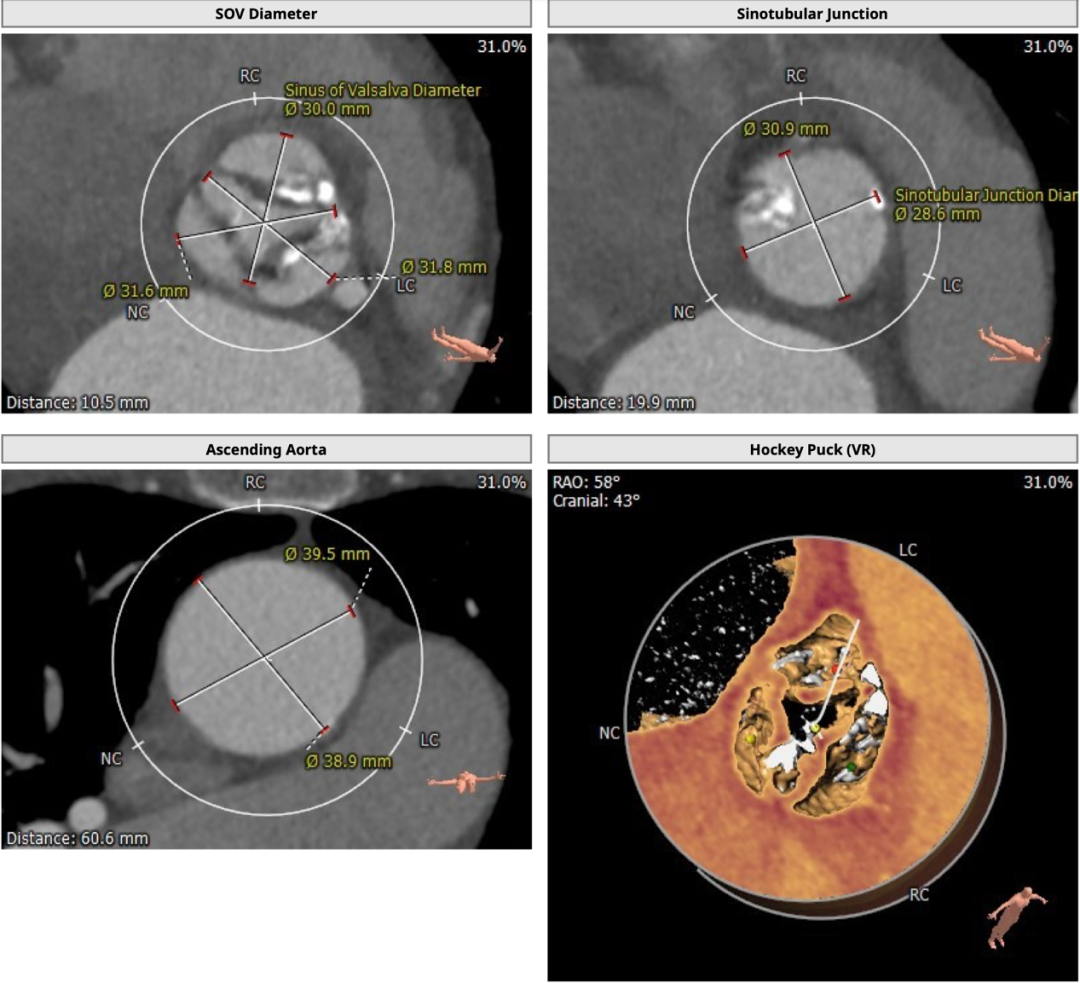

术前CT

为TYPE1型二叶式主动脉瓣,左右融合钙化嵴,钙化较重,瓣环周长获得平均直径25.1mm,左右冠脉开口高度分别为11.1和16.1mm。左冠开口水平可见瓣叶,有堵塞风险。双侧股动脉无明显钙化迂曲,左右最细处分别为5.7和5.8mm。

为三叶式主动脉瓣,瓣叶钙化较重,瓣环周长获得平均直径23.5mm,左右冠脉开口高度分别为11.2和16.4mm。瓣叶冗长,左冠开口水平可见瓣叶,左冠有堵塞风险。双侧股动脉走行流畅,无明显钙化迂曲,左右最细处分别为6.5和6.6mm。